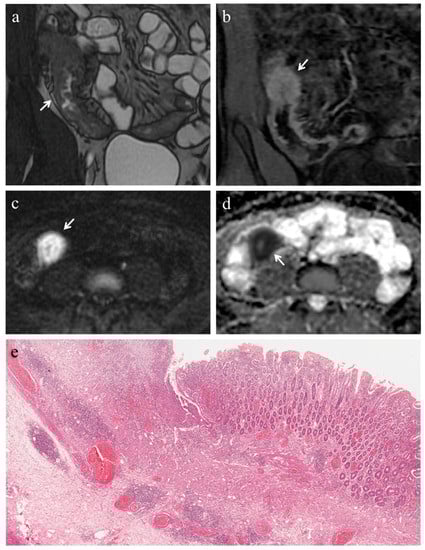

Figure 1. (af). MRE in a 49-year-old woman with CD: severe predominantly fibrotic stricture of the terminal ileum. (a) Coronal fast imaging employing steady state acquisition (FIESTA) image shows wall thickening with noticeable narrowing of the lumen in the terminal ileum (white arrow); note the dilatation (>30 mm) of the upstream bowel loop (white asterisk). (b) Axial and (c) coronal contrast-enhanced fat-suppressed T1-weighted images demonstrate homogeneous enhancement of terminal ileum (white arrows). (d) Axial DW image (b = 800 s/mm2) and (e) corresponding ADC map show the same intestinal segment demonstrating restricted diffusion with high signal intensity (white arrow) on the DWI image and low signal intensity (white arrow) on the ADC map (mean ADC value 0.745 × 10−3 mm2/s). (f) Histopathological section from the ileal stricture: hematoxylin and eosin-stained sample (H&E 10×). CD exhibiting severe fibrosis (FS = 2) and moderate inflammation (AIS = 7): muscular layers dissected by dense fibrotic tissue on the left, mucosal ulceration and moderate inflammatory infiltration on the right.

In 18 (78.3%) ileal segments, inflammation and fibrosis coexisted (Figure 1 and Figure 2), in 5 (21.7%) cases inflammatory alterations without fibrosis were found (Figure 3), whereas under no circumstances was fibrosis without inflammation encountered. No significant correlation was highlighted between AIS and FS (p = 0.22).

Pattern of enhancement. The diseased bowel wall showed the following enhancement patterns: homogeneous in 6 cases (26.1%) (Figure 1b,c, Figure 3b), mucosal in 8 cases (34.8%) (Figure 2c) and layered in 9 cases (39.1%). Pattern of enhancement did not show significant variations according to AIS (p = 0.56) or FS (p = 0.49).

Pre-stenotic luminal diameter. Maximum caliber of pre-stenotic upstream bowel (mean 33 ± 14 mm, range 17–80 mm) did not correlate with inflammation score (p = 0.50). On the other hand, pre-stenotic bowel dilatation positively correlated with the fibrosis score (p = 0.002): upstream bowel dilatation increased according to fibrosis grade (Figure 1a). In particular, pre-stenotic luminal diameter was higher in patients with severe fibrosis than in those with none or mild/moderate fibrosis (p < 0.05) (Figure 4, Panel a). The mean pre-stenotic luminal diameters were 25 ± 4 mm, 27 ± 5 mm and 47 ± 18 mm for none, mild/moderate and severe FS, respectively. Moreover, this measurement showed a high accuracy (AUC 0.75, p < 0.001) for discriminating between none and mild/moderate–severe bowel wall fibrosis; using a threshold value of 30 mm, the sensitivity and specificity were 100% and 44%, respectively (Figure 5, Panel a).

3.4. Analysis of DWI Quantitative Measures (ADC)

The mean size of the ROIs used to measure the ADC value in the diseased bowel wall was 48 ± 22 mm2. The overall mean of ADC values was 1.168 ± 0.181 × 10−3 mm2/s (range 0.745–1.473 × 10−3 mm2/s). No significant correlation was found between ADC and inflammation score (p = 0.41). The ADC value was negatively correlated with the fibrosis score (p < 0.001). The ADC value was different between FS grades (p < 0.05) (Figure 4, Panel b). The means of the ADC values were 1.371 × 10−3 mm2/s for none, 1.224 × 10−3 mm2/s for mild/moderate and 0.936 × 10−3 mm2/s for severe FS. ADC values showed a high accuracy (AUC 0.97, p < 0.001) for discriminating between none and mild/moderate–severe bowel wall fibrosis. Using a threshold ADC value of 1.300 × 10−3 mm2/s, the sensitivity and specificity were 80% and 100%, respectively (Figure 5, Panel b). Qualitative and quantitative MRE findings are summarized in Table 3.